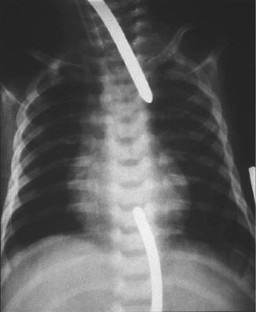

Fig. 1

Fig. 2

Fig. 3